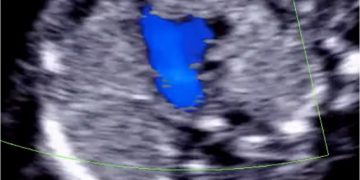

How To Do Settembre 2022: corretto settaggio del Doppler in ostetricia

Cari soci, questo mese un nuovo video "How to do", sul corretto settaggio del Doppler in Ostetricia. Grazie a Paola Quaresima! Il video è accessibile ai soli soci SIEOG attraverso...